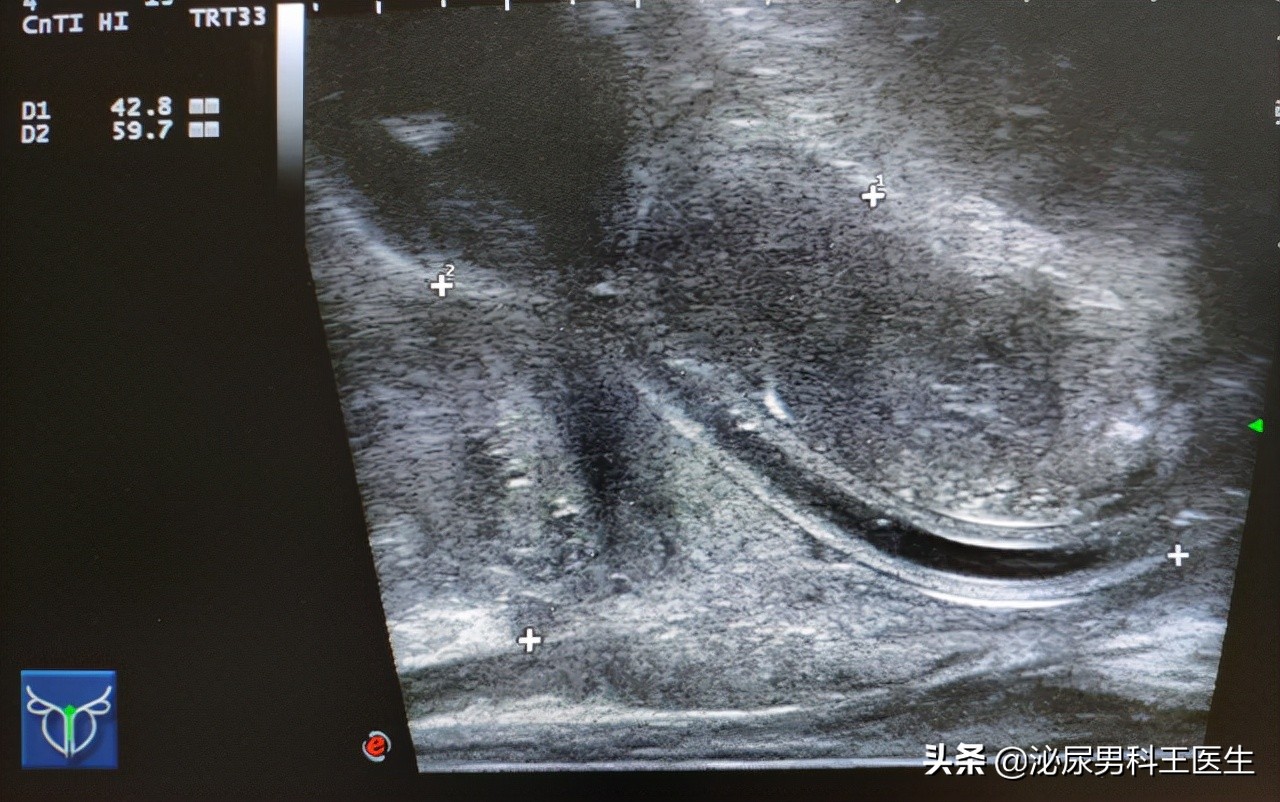

在诊疗的过程中,朱大爷自述上述症状,同时没有三高病史,无吸烟史、药物过敏史、家族遗传史等,在进行了一些类的专科检查和辅助检查后,前列腺MRI示前列腺体积增大,约为4.1cm ×2.8cm ×3.1cm,向膀胱内突入上面分布了多发类的异常信号,而且通过扫描可见左侧的腹股沟区域有明显的异常信号。

综合尿动力等检查项目,朱大爷被诊断为良性的前列腺增生,同时由于他的膀胱收缩力尚可,又没有手术禁忌症,故而医生为朱大爷安排了入院手术。